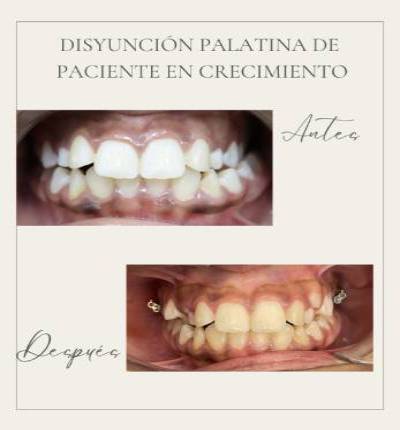

Ortodoncia y Odontopediatría

Ofrecemos tanto ortodoncia invisible con alineadores como ortodoncia fija con brackets.

Evaluamos cada caso y te recomendamos el más adecuado para ti. También ortodoncia para los más pequeños y los pacientes en crecimiento.